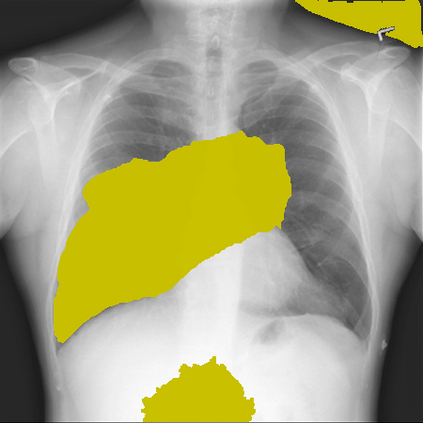

The remarkable success of deep learning has prompted interest in its application to medical imaging diagnosis. Even though state-of-the-art deep learning models have achieved human-level accuracy on the classification of different types of medical data, these models are hardly adopted in clinical workflows, mainly due to their lack of interpretability. The black-box-ness of deep learning models has raised the need for devising strategies to explain the decision process of these models, leading to the creation of the topic of eXplainable Artificial Intelligence (XAI). In this context, we provide a thorough survey of XAI applied to medical imaging diagnosis, including visual, textual, example-based and concept-based explanation methods. Moreover, this work reviews the existing medical imaging datasets and the existing metrics for evaluating the quality of the explanations. In addition, we include a performance comparison among a set of report generation-based methods. Finally, the major challenges in applying XAI to medical imaging and the future research directions on the topic are also discussed.